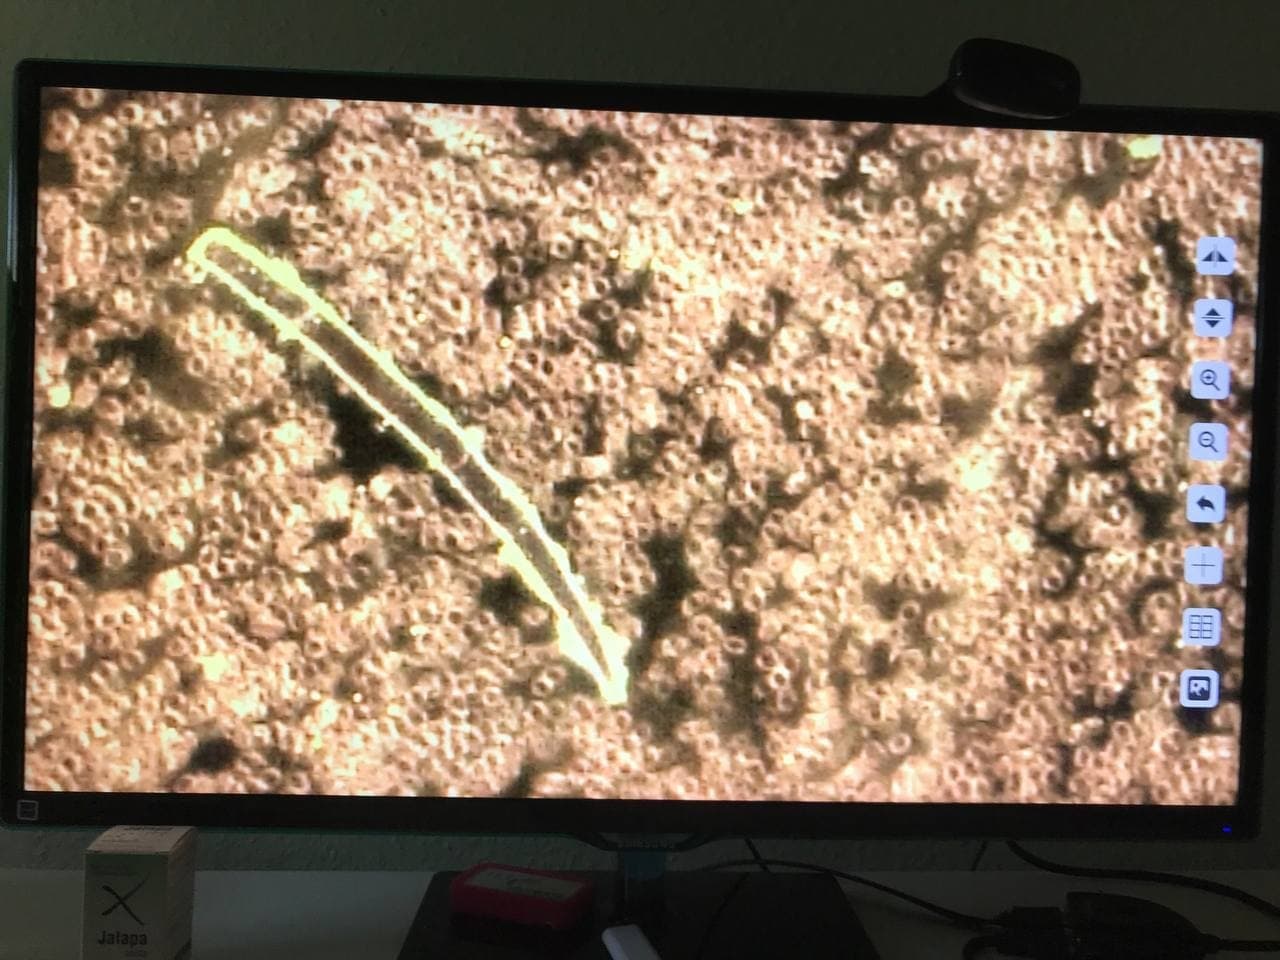

GENimpfschaden

im Blutbild einer GENgeimpften Person

15.9.2021: 9 Fotos

Impfschäden Schweiz

Coronaimpfung, [15.09.21 13:19]

https://t.me/Impfschaden_Corona_Schweiz/21521

[Weitergeleitet aus Holger Fischer

Rechtsanwalt (Maya Stella)]

Im folgenden wieder Blutbilder von Blut von

Geimpften, mit Verunreinigungen

(Dunkelfeldmikroskopie) |

GENimpfschaden

im Blutbild 15.9.2021: Foto 1

Impfschäden Schweiz Coronaimpfung, [15.09.21

13:19]

https://t.me/Impfschaden_Corona_Schweiz/21522

[Weitergeleitet aus Holger Fischer Rechtsanwalt

(Maya Stella)]

Scheibenartiges Gebilde mit leuchtenden Punkten

GENimpfschadne im Blutbild 15.9.2021: Foto 1

[37] |

GENimpfschaden

im Blutbild 15.9.2021: Foto 2

Impfschäden Schweiz Coronaimpfung, [15.09.21

13:19]

https://t.me/Impfschaden_Corona_Schweiz/21523

[Weitergeleitet aus Holger Fischer Rechtsanwalt

(Maya Stella)]

Scheibenartige Form mit Spike Proteinen (?)

GENimpfschaden im Blutbild 15.9.2021: Foto 2

[38]

|

GENimpfschaden

im Blutbild 15.9.2021: Foto 3

Impfschäden Schweiz Coronaimpfung, [15.09.21

13:19]

https://t.me/Impfschaden_Corona_Schweiz/21524

[Weitergeleitet aus Holger Fischer Rechtsanwalt

(Maya Stella)]

Seltsame Form über den Erys

GENimpfschaden im Blutbild 15.9.2021: Foto 3

[39] |

GENimpfschaden

im Blutbild 15.9.2021: Foto 4

Impfschäden Schweiz Coronaimpfung, [15.09.21

13:19]

https://t.me/Impfschaden_Corona_Schweiz/21525

[Weitergeleitet aus Holger Fischer Rechtsanwalt

(Maya Stella)]

Seltsame Form im Blut Erys wirken wie tot

GENimpfschaden im Blutbild 15.9.2021: Foto 4

[40] |

GENimpfschaden

im Blutbild 15.9.2021: Foto 5

Impfschäden Schweiz Coronaimpfung, [15.09.21

13:19]

https://t.me/Impfschaden_Corona_Schweiz/21526

[Weitergeleitet aus Holger Fischer Rechtsanwalt

(Maya Stella)]

Stechapfelformen

GENimpfschaden im Blutbild 15.9.2021: Foto 5

[41] |

GENimpfschaden

im Blutbild 15.9.2021: Foto 6

Impfschäden Schweiz Coronaimpfung, [15.09.21

13:19]

https://t.me/Impfschaden_Corona_Schweiz/21527

[Weitergeleitet aus Holger Fischer Rechtsanwalt

(Maya Stella)]

spitze Gebilde

GENimpfschaden im Blutbild 15.9.2021: Foto 6

[42]

|

GENimpfschaden

im Blutbild 15.9.2021: Foto 7

Impfschäden Schweiz Coronaimpfung, [15.09.21

13:19]

https://t.me/Impfschaden_Corona_Schweiz/21528

[Weitergeleitet aus Holger Fischer Rechtsanwalt

(Maya Stella)]

Unbekanntes Objekt im Blut

GENimpfschaden im Blutbild 15.9.2021: Foto 7

[43]

|

GENimpfschaden

im Blutbild 15.9.2021: Foto 8

Impfschäden Schweiz Coronaimpfung, [15.09.21

13:19]

https://t.me/Impfschaden_Corona_Schweiz/21529

[Weitergeleitet aus Holger Fischer Rechtsanwalt

(Maya Stella)]

unnatürliche Form

GENimpfschaden im Blutbild 15.9.2021: Foto 8

[44] |

GENimpfschaden

im Blutbild 15.9.2021: Foto 9

Impfschäden Schweiz Coronaimpfung, [15.09.21

13:19]

https://t.me/Impfschaden_Corona_Schweiz/21530

[Weitergeleitet aus Holger Fischer

Rechtsanwalt (Maya Stella)]

vermehrt hell leuchtende Gebilde

GENimpfschaden im Blutbild 15.9.2021: Foto 9

[45] |

GENimpfschaden Blut nach GENimpfung Schweiz

6.11.2021: Verklebte Blutkörperchen und Gegenstände im

Blut

Impfschäden Schweiz Coronaimpfung, [06/11/2021 03:17 P.M.]

https://t.me/Impfschaden_Corona_Schweiz/28793

Diese Dunkelfeld-Bilder wurden am 28.09.2021 vom Blut eines

18 jährigen Mannes aufgenommen, der 10 Tage zuvor die erste

Dosis mit Biontech/Pfizer bekommen hatte. Sie zeigen

Anomalien, die die Untersuchende (Name ist Kanalbetreiberin

bekannt) laut ihrer Aussage in ihrer langen Zeit der Praxis

noch nie zuvor gesehen hat. Auch derjenige, der die Bilder

direkt vom Bildschirm abfotografiert hat, ist pers. bekannt.